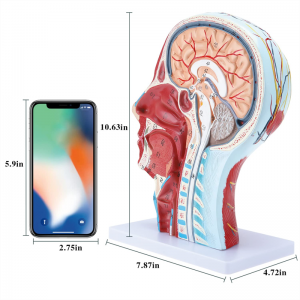

| Ubukhulu | 21 * 12 * 27cm |

【1: 1 I-Lifesise】 Ingxenye ye-Median ye-Median ye-1: 1 yemvelo enkulu yemvelo & imodeli yemisipha yemisipha ye-nearal ye-nearal ye-nearal (uhlangothi olungakwesokudla). Umsebenzi omuhle. Ukunikeza uhla oluphelele lwezici ze-anatomical.

Le modeli iyinhloko enkulu yemvelo nemodeli ye-neurovascular yemisipha eyindilinga, isakhi esingu-1, ekhombisa imininingwane yekhanda lelungelo lomuntu kanye nentamo kanye nengxenye ye-Median Sagittal, okubandakanya imisipha engemihle yobuso, imithambo ephakeme yobuso obukhulu bobuso kanye nesikhumba, izinzwa nokwakheka kwempilo kwe-parotid gland kanye nepheshana lokuphefumula elingaphezulu, kanye nesakhiwo seSigaba se-sagittal somgogodla wesibeletho